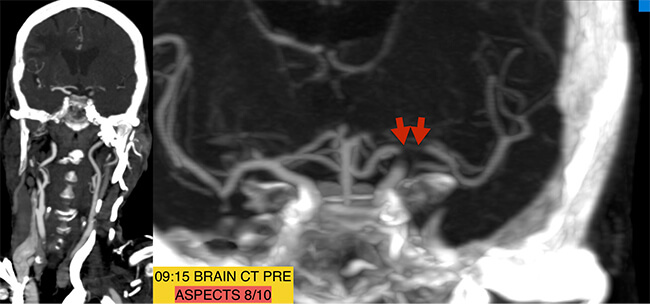

Ακολούθησε αξονική αγγειογραφία με ταχεία έγχυση σκιαγραφικού. Διαπιστώθηκε θρόμβος στον διχασμό της αριστερής έσω καρωτίδος (κόκκινα βέλη)

και καλή παράπλευρη κυκλοφορία που σημαίνει ότι υπήρχε βιώσιμο εγκεφαλικό παρέγχυμα στην κατανομή του αποφραγμένου αγγείου, το οποίο όμως ισχαιμεί (γι´ αυτό και τα βαρειά συμπτώματα της ασθενούς). Η ασθενής βρίσκεται σε άμεσο κίνδυνο να υποστεί μη αναστρέψιμη νέκρωση. Μεταφέρεται άμεσα στον αγγειογράφο.